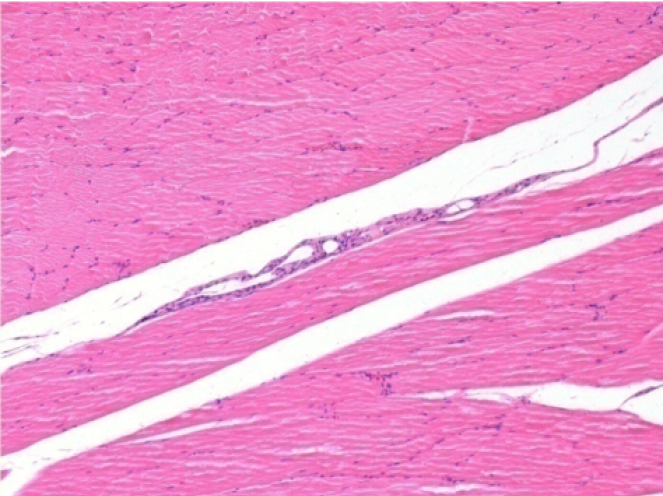

Sx : Controllo-100x-Giorno210

Dx:100x-Giorno210

Sx :Controllo 50x-Giorno210

Dx:50X-Giorno210

Restitutio ad integrum completo dopo 7 mesi